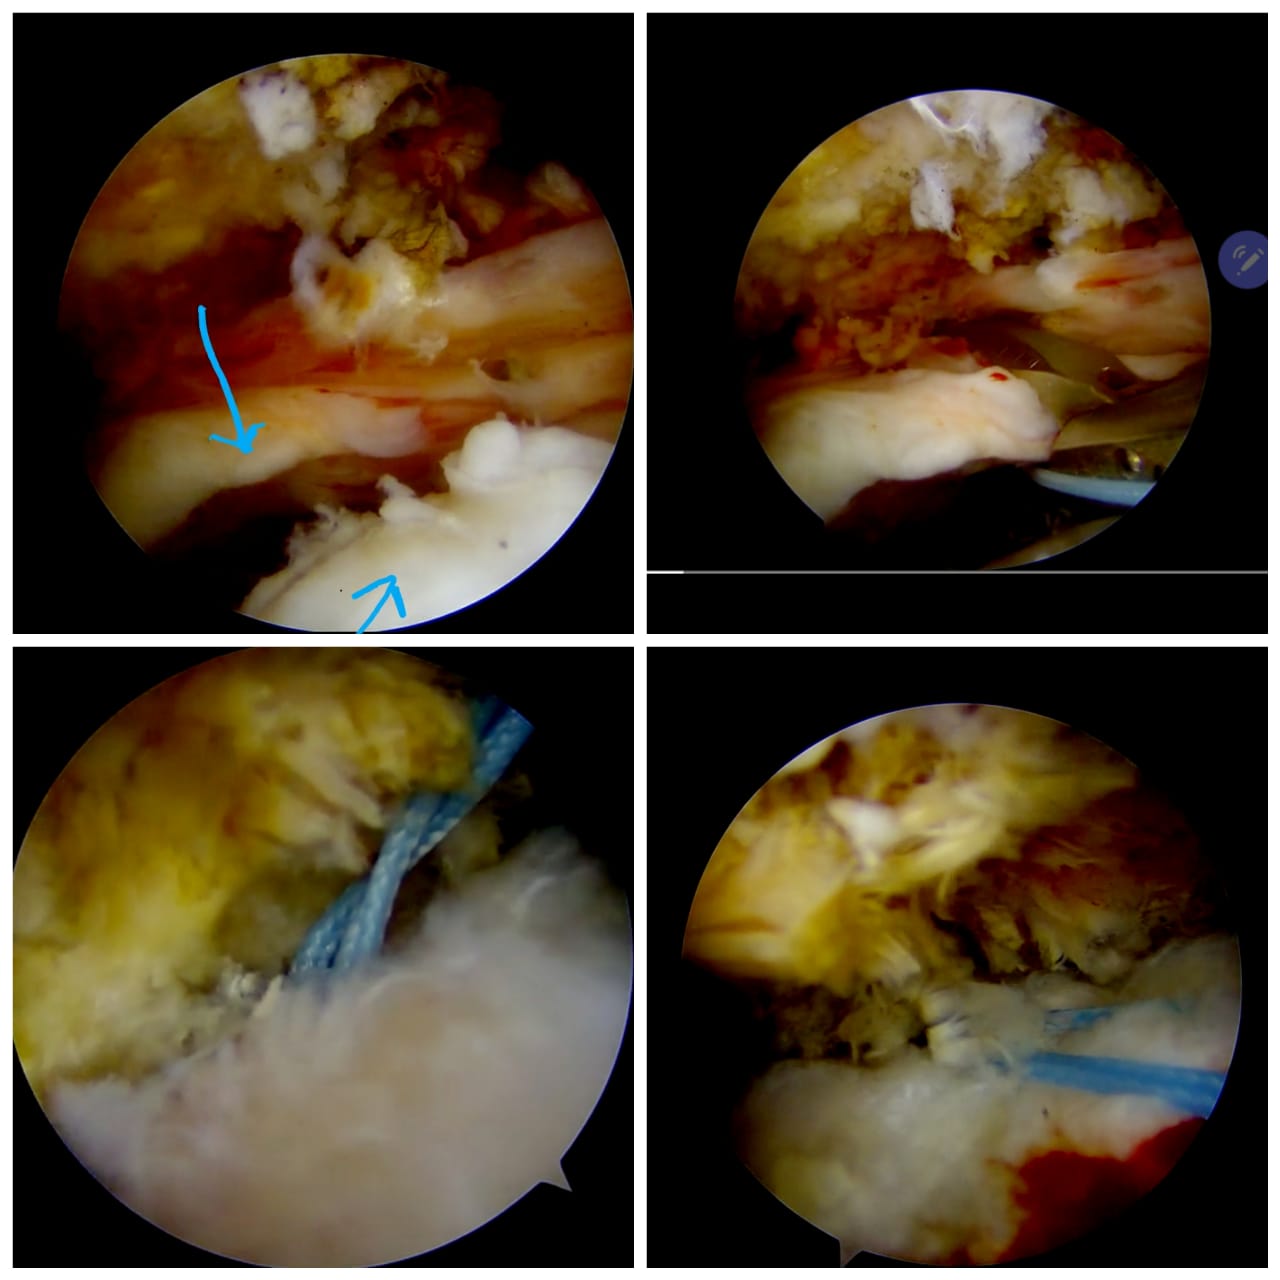

Read MoreHistory: A 65 years old man was unable to sleep or put any pressure on his shoulders due to severe shoulder tear. Case: This man was operated by Dr. Amyn Rajani, Joint Replacement & Arthroscopy Specialist in COVID-19 times.…